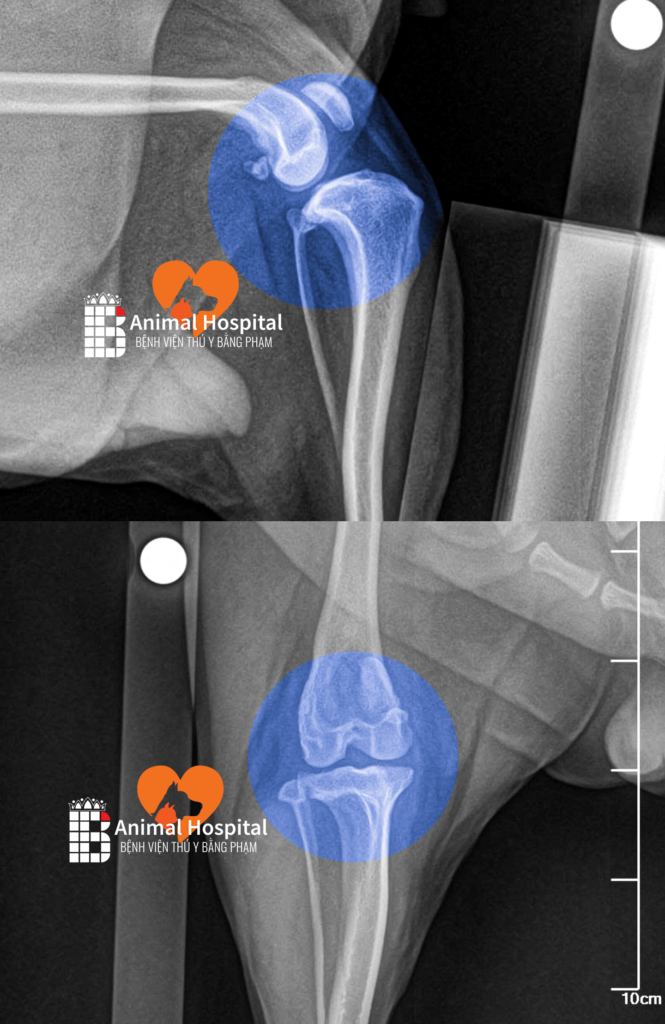

Tại Bệnh viện Thú y Bằng Phạm, kết quả X-quang cho thấy Bông Lúa mắc phải hai tổn thương nghiêm trọng cùng lúc: trật xương bánh chè độ ba và đứt hoàn toàn dây chằng chéo trước.

- Với chứng trật xương bánh chè: Trong trường hợp bình thường, xương bánh chè phải nằm chính giữa rãnh trên xương đùi để khớp vận hành trơn tru, nhưng ở Bông Lúa, xương bánh chè đã trượt hoàn toàn ra khỏi rãnh và bị khóa cứng ở vị trí sai, khiến bé không thể duỗi thẳng chân và chỉ có thể di chuyển bằng ba chân còn lại.

- Với chấn thương đứt dây chằng: Dây chằng chéo trước có vai trò như một dây neo quan trọng, giữ cho xương chày và xương đùi liên kết chặt chẽ với nhau – khi dây chằng này đứt, xương chày mất sự kiềm chế và trượt về phía trước mỗi khi chịu lực, khiến hai khúc xương không còn khớp đúng trục và toàn bộ khớp gối mất ổn định hoàn toàn.